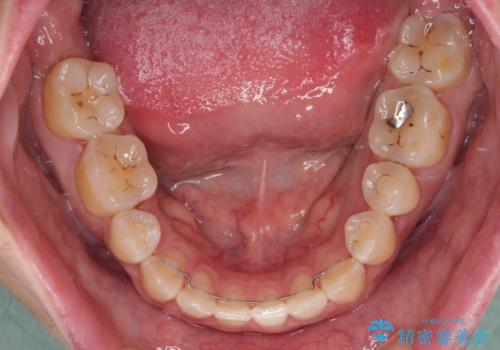

舌の突出癖改善のトレーニングが全くうまくできず、治療期間が長期化しました。

早く治療を終えたいとの要望があり、トレーニング次第と伝えるとようやく練習をするようになり、その後は速やかに上下の隙間が改善されました。